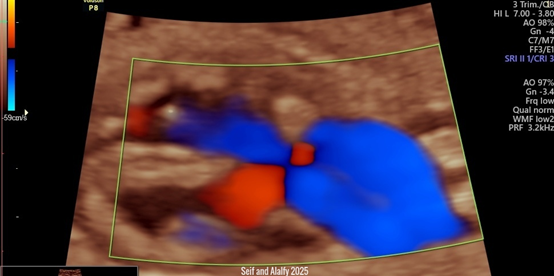

Figure 2 Shows 3D US with Color Doppler illustrating Seif and Alalfy twist sign ,this technique describes an oblique view that illustrates the right and left ventricles with the interventricular septum and the atrioventricular valves with the aorta and pulmonary arteries crossing each others and till they form the v-sign ending to the ductus arteriosus.

This sign can be approached by sweeping the probe to get the optimum oblique view in the heart to illustrate right, left ventricles, interventricular septum, atrioventricular valves with the aorta and pulmonary arteries crossing each others.

The Seif and Alalfy twist sign can thus demonstrates a normal four chamber view and outflow tracts and 3 vessel views in a very short time Compared to the illustrated fetal echocardiography.